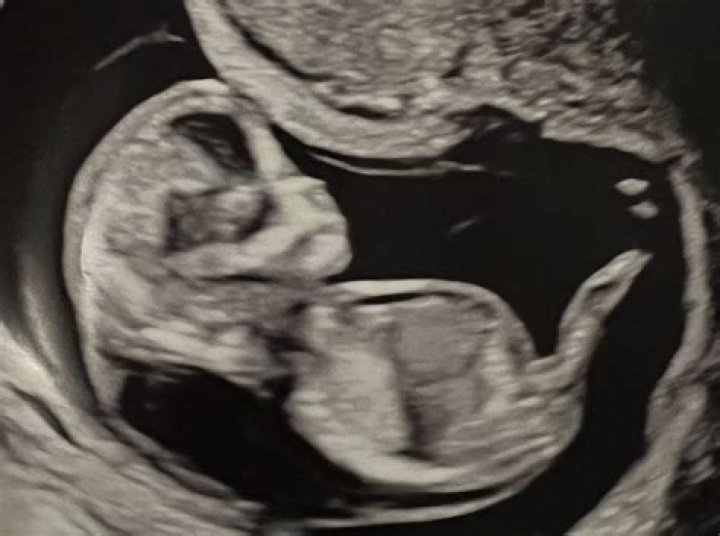

After sharing an ultrasound of their baby, Chip & Joanna Gaines have received some startling comments! Fans believe the pic shows the baby could be in ser...